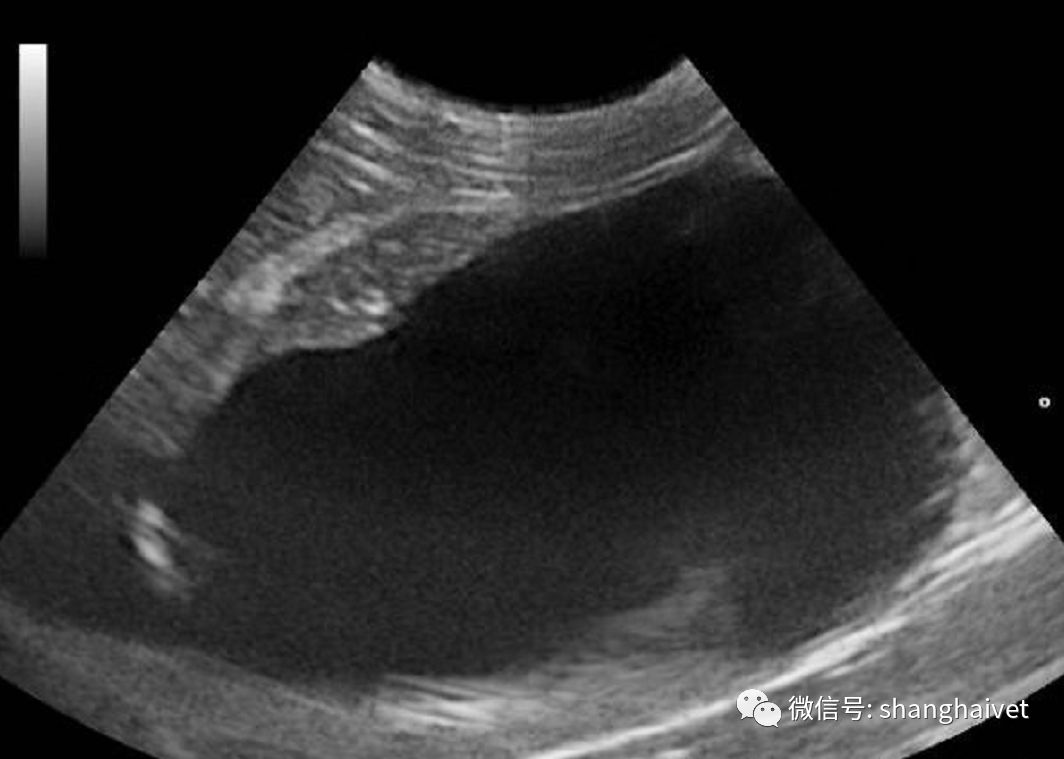

B超扫描显示肝内呈低回声团块。

▲B超扫描结果